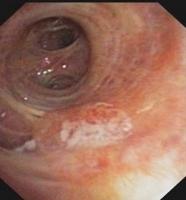

Squamous cell (epidermoid) carcinoma